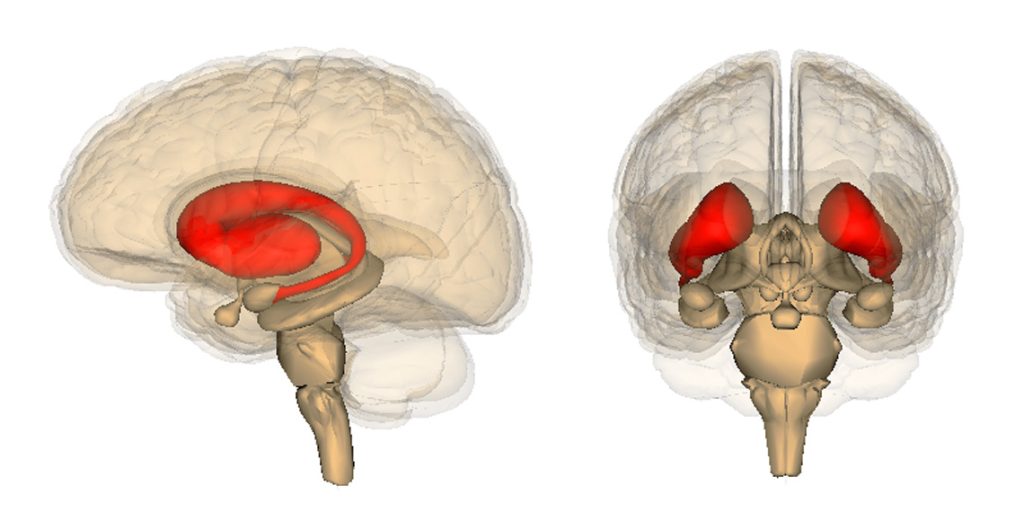

One way to measure the brain’s response to reward is to Ventral striatum – A key area of the reward system that controls pleasure.

The aim of our study was to investigate what happens in the ventral striatum during momentary mood changes in 21 subjects with bipolar disorder and 21 control subjects. We wanted to measure this down to the second in response to monetary reward.

In all participants, the brain regions involved in the experience and recognition of temporary mood states Anterior insula.

However, during periods of upward momentum, when participants won multiple times, the ventral striatum showed strong positive signals only in participants with bipolar disorder, meaning that they experienced a heightened sense of reward.

They also found that participants with bipolar disorder had reduced communication between the ventral striatum and the anterior insula, whereas in controls, both regions fired in an integrated manner.